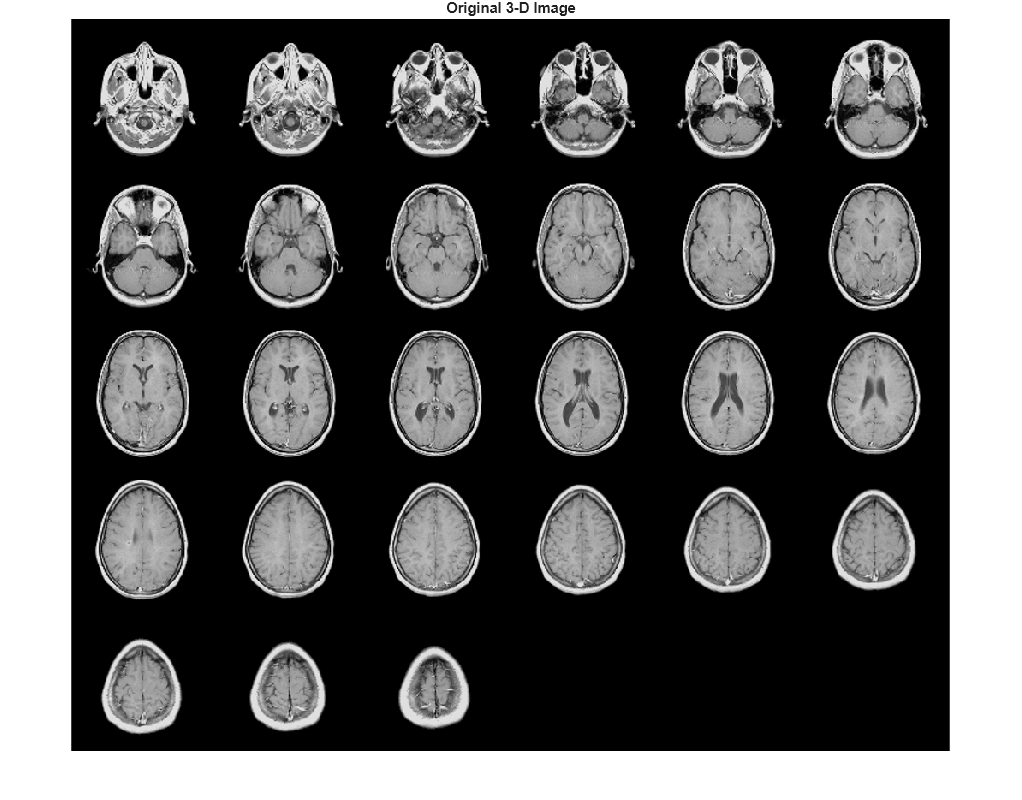

N 次元グレースケール イメージをワークスペースに読み込みます。また、参照ヒストグラムを提供するグレースケール イメージも読み込みます。

load mri D load mristack

元のボリュームをスライスとして表示します。

figure montage(D,'DisplayRange',[]) title('Original 3-D Image')